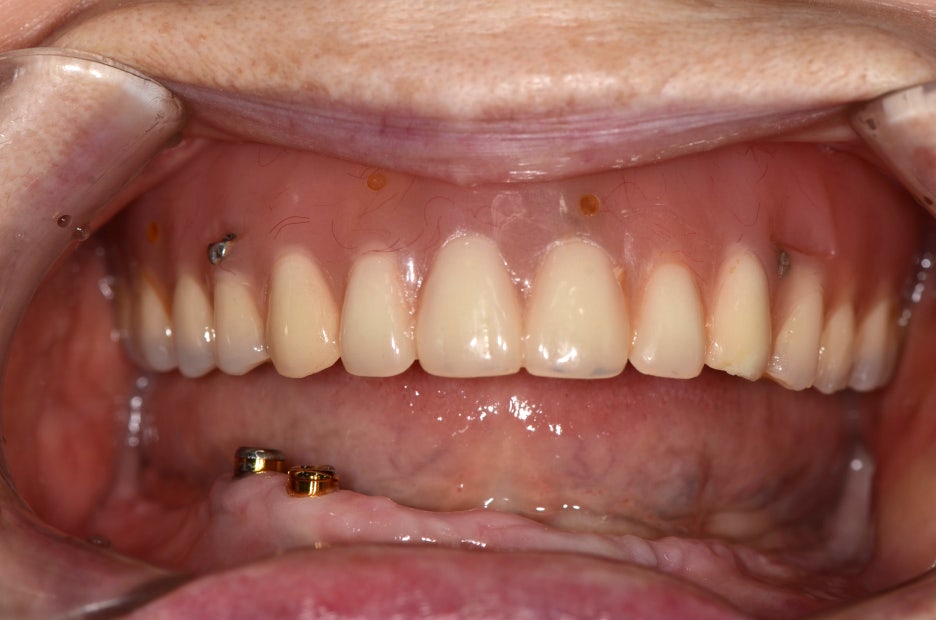

이번에는 틀니 대신 전체임플란트를 원하셔서 수술 전 정밀한 진단을 한 후 수술을 계획을 세워드리기로 했어요.

진단 결과 현재 식립 되어 있는 임플란트는 상태가 양호하고 본원의 임플란트와 호환이 가능하여 지대주만 재제작 하여 사용하기로 하였고, 4개의 임플란트를 추가로 식립하여 풀아치임플란트를 진행하기로 했어요.

위 하악 사진을 보시면 오랜 시간 틀니를 사용하여 잇몸뼈가 상당히 소실된 것을 볼 수 있는데요. 오랜 세월 사용하게 되면 잇몸이 틀니에 눌려 수축할 수 있어요.

이럴 경우 임플란트 식립 시 문제가 될 수 있는데 환자분의 경우에도 잇몸뼈가 부족하여 치조골 이식을 진행한 후 임플란트를 식립하였습니다.